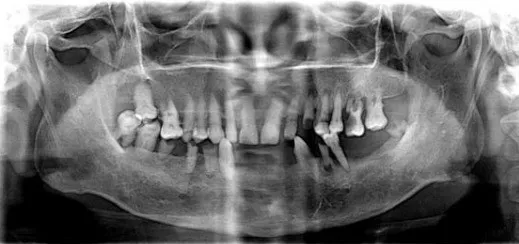

然后是牙齿全景影像图和分析结果标识,哪颗牙缺失了,根尖周炎的位置,能让你比照镜子还要看的清楚自己牙齿的样子。

▲ 常见的牙片是二维的

CBCT的出现彻底改变了传统口腔颌面放射学设备仅能提供二维图像的历史,可以三维显示病变结构,大大提高了诊断能力。